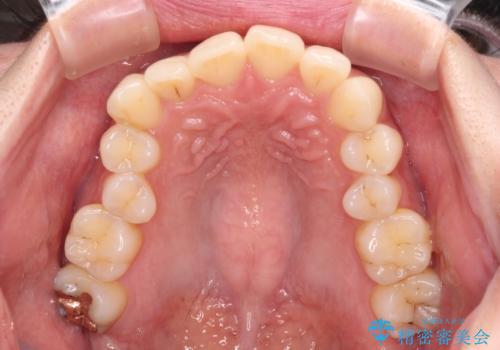

- 前歯のデコボコと強い咬みしめを気にして来院された患者様です。

インビザラインを用いて、前歯の叢生を解消するとともに、ディープバイトを改善していくこととしました。

海外へ転居する予定があったため、1日22時間以上の装着時間をしっかりと守っていただき、予定期間よりも早く、思っていた以上にきれいに仕上げることができました。